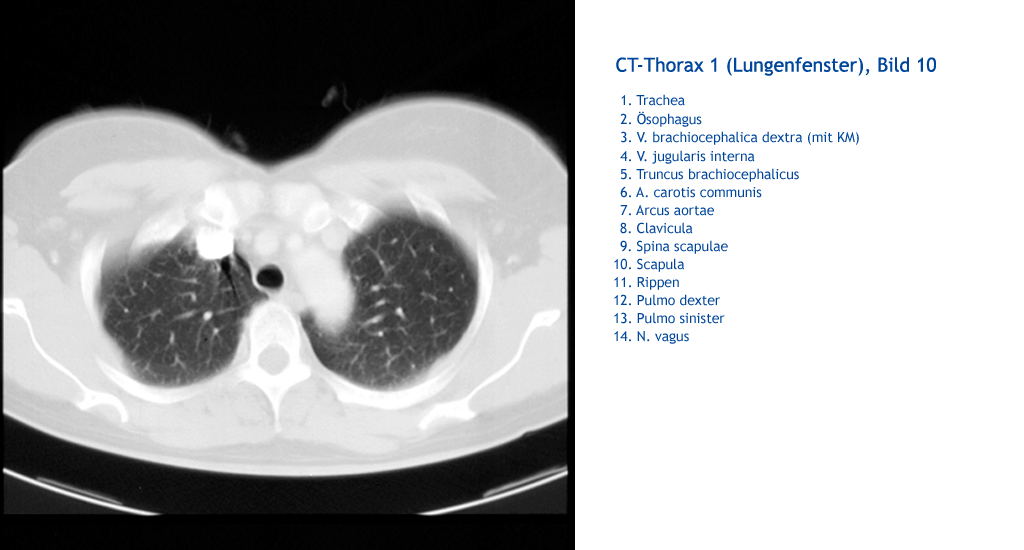

N. vagus Pulmo sinister Pulmo dexter Rippen Rippen Rippen Scapula Spina scapula Clavicula Arcus aortae A. carotis communis Truncus brachiocephalicus V. jugularis interna V. brachiocephalica dextra (mit KM) Ösophagus Trachea